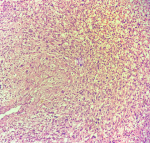

Diagnostic assessment: the patient was admitted under the Department of Neurosurgery. All routine investigations, including chest X-ray and electrocardiography, were conducted and were found to be within normal limits. A previously performed MRI of the brain revealed an extra-axial lesion in the left cerebellopontine (CP) angle with a broad-based dural attachment, intense post-contrast enhancement, and a positive dural tail sign. The lesion caused indentation and distortion of the brainstem, with no evidence of vertebrobasilar abnormality, findings suggestive of a meningioma (Figure 1). Based on the clinical presentation and imaging features, a preliminary diagnosis of a left CP angle tumour was made, and the patient was scheduled for retro-mastoid craniotomy with excision of the left CP angle tumour. Intraoperatively, a well-encapsulated, greyish-white, globular mass approximating 2.4 x 1.9 cm was noted. The tumour was moderately vascular, firm in consistency, and adhered to the trigeminal nerve. The surgery was uneventful, with no trace of active bleeding or cerebrospinal fluid leakage prior to closure. The excised tissue was submitted for histopathological examination. Grossly, the specimen comprised multiple, irregular, greyish-brown fragments measuring approximately 2 x 1 x 0.5 cm (Figure 2). Microscopic evaluation demonstrated alternate hypocellular and hypercellular areas producing a marbling effect (Figure 3(A, B)). Sections also showed a uniform population of spindle-shaped cells with slender, pleomorphic, hyperchromatic nuclei displaying folded contours (Figure 4). Immunohistochemical evaluation was carried out to further substantiate the diagnosis. The cells demonstrated strong positivity for vimentin (Figure 5 A), a markedly raised Ki-67 index of about 90% (Figure 5 B), while being negative for SOX-10 (Figure 5 C) and S-100 (Figure 5 D).

Figure 3: microscopic examination [H&E, 10X]- alternate hypocellular (green arrows) and hypercellular areas (black arrows) producing a marbling effect

Figure 4: microscopic examination [H&E, 40X]- uniform population of spindle-shaped cells exhibiting slender, pleomorphic, hyperchromatic nuclei with folded contours